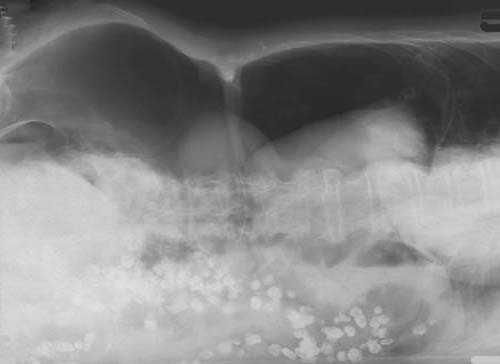

Abdomen-Übersicht in Links-Seitenlage

Nachweis freier

Luft in der Bauchhöhle

unter dem rechten

Zwerchfellschenkel. Fleckförmige

Kontrastmittelansammlungen im Colon descendens und Colon sigmoideum

bei Z.n. Colon-Kontrastmitteluntersuchung (mit Barium) vor mehreren Tagen.

Pneumoperitoneum,

Divertikulose des Colon descendens und Colon sigmoideum